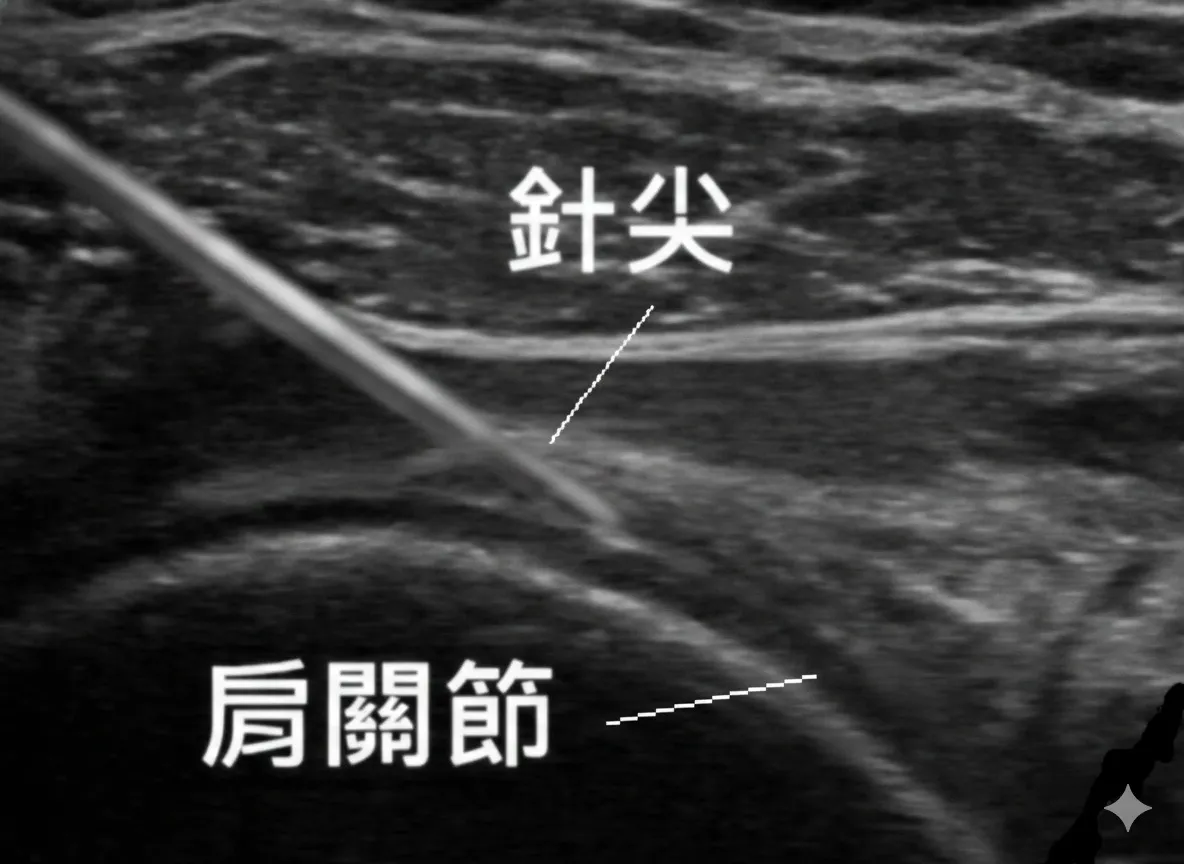

肩關節擴張術的原理,是利用液體的壓力將緊繃沾黏的肩關節囊「撐開」。然而,肩關節囊深且空間狹小,宸新復健科堅持拒絕憑手感的盲打,全療程採用高解析骨骼肌肉超音波導引,邊掃描邊打針,確保擴張液精準注入關節腔內,大幅提升治療成功率。研究顯示,超音波導引注射的關節腔內準確率可達 92.5%,顯著優於徒手盲打的 72.5 [5]。

精準撐開沾黏: 醫師透過「第三隻眼」監控,確認針尖進入關節腔後,注入大量擴張液(食鹽水、葡萄糖或消炎藥)。在螢幕上可直接看到關節囊被液體撐開的瞬間,確保沾黏組織被有效分離。2023 年系統性回顧與統合分析確認,擴張術在改善肩關節失能指數與被動外旋方面,優於單純類固醇注射[4]。

- 超音波定位: 側臥或坐姿,醫師掃描肩關節囊位置與周邊神經血管。

- 擴張注射: 局部麻醉後,在動態顯影下注入擴張液。過程中會感到肩膀內部有腫脹痠痛感,代表沾黏正在被撐開,此為正常現象。

實證:Patel et al. 的大體研究顯示,超音波導引的關節腔注射準確率為 92.5%,而徒手盲打僅 72.5%(p=0.02)[5];回顧 12 項研究亦指出,盲打的平均準確率僅 79%,影像導引則可達 95%[13]。當針頭未能精準進入關節腔,擴張液可能注入關節外,治療效果大打折扣。